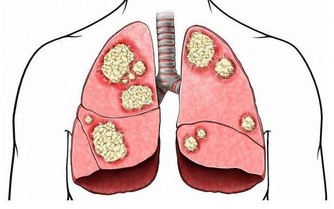

牙結石會不斷刺激牙周組織,並會壓迫牙齦影響血液迴圈,

造成牙周組織的病菌感染,引起牙齦發炎萎縮,形成牙周囊袋。

網絡圖片

當牙周囊袋形成後,更易使食物殘渣、牙菌斑和牙結石等堆積,

這種新的堆積又更進一步的破壞更深的牙周膜,

最終會讓牙周組織全部破壞殆盡,而使牙齒難逃拔除的惡運。